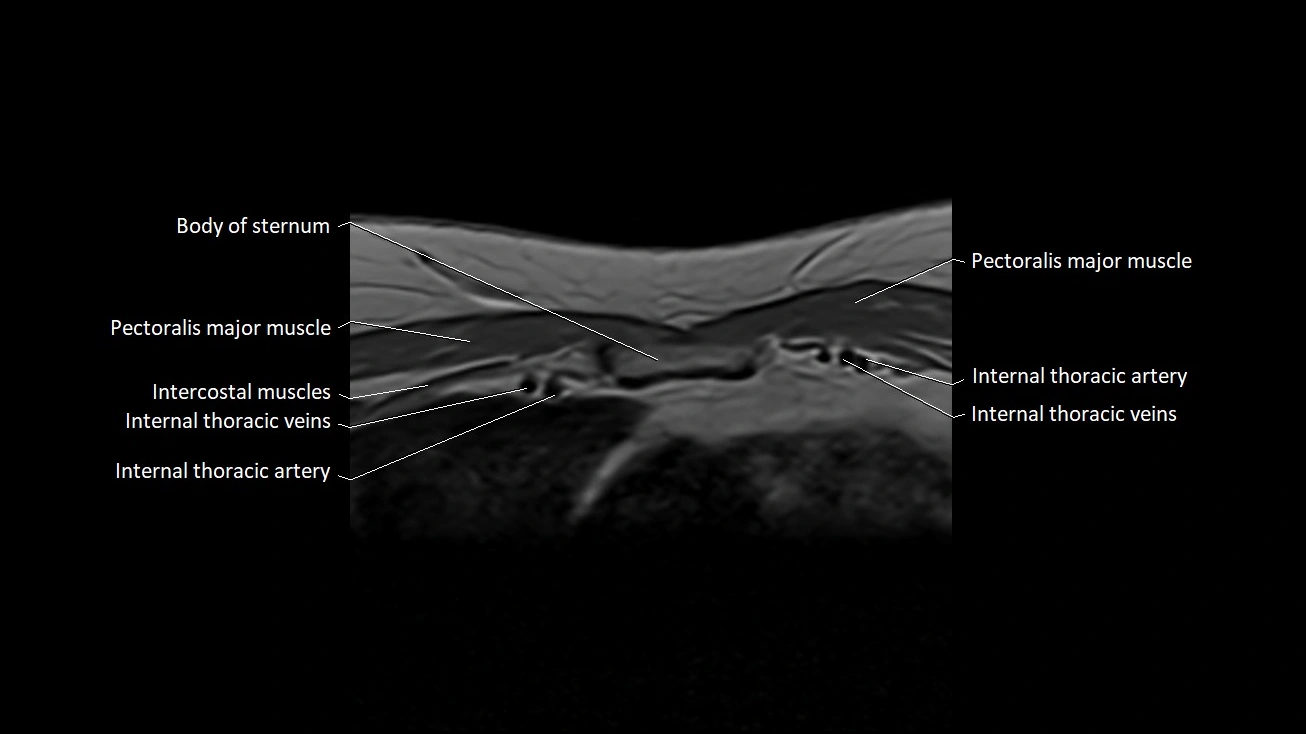

MRI images

image